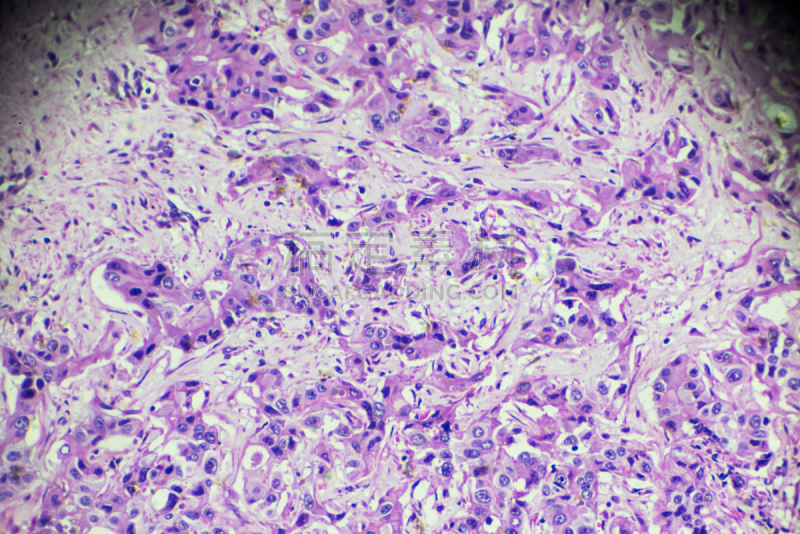

详情

JPG